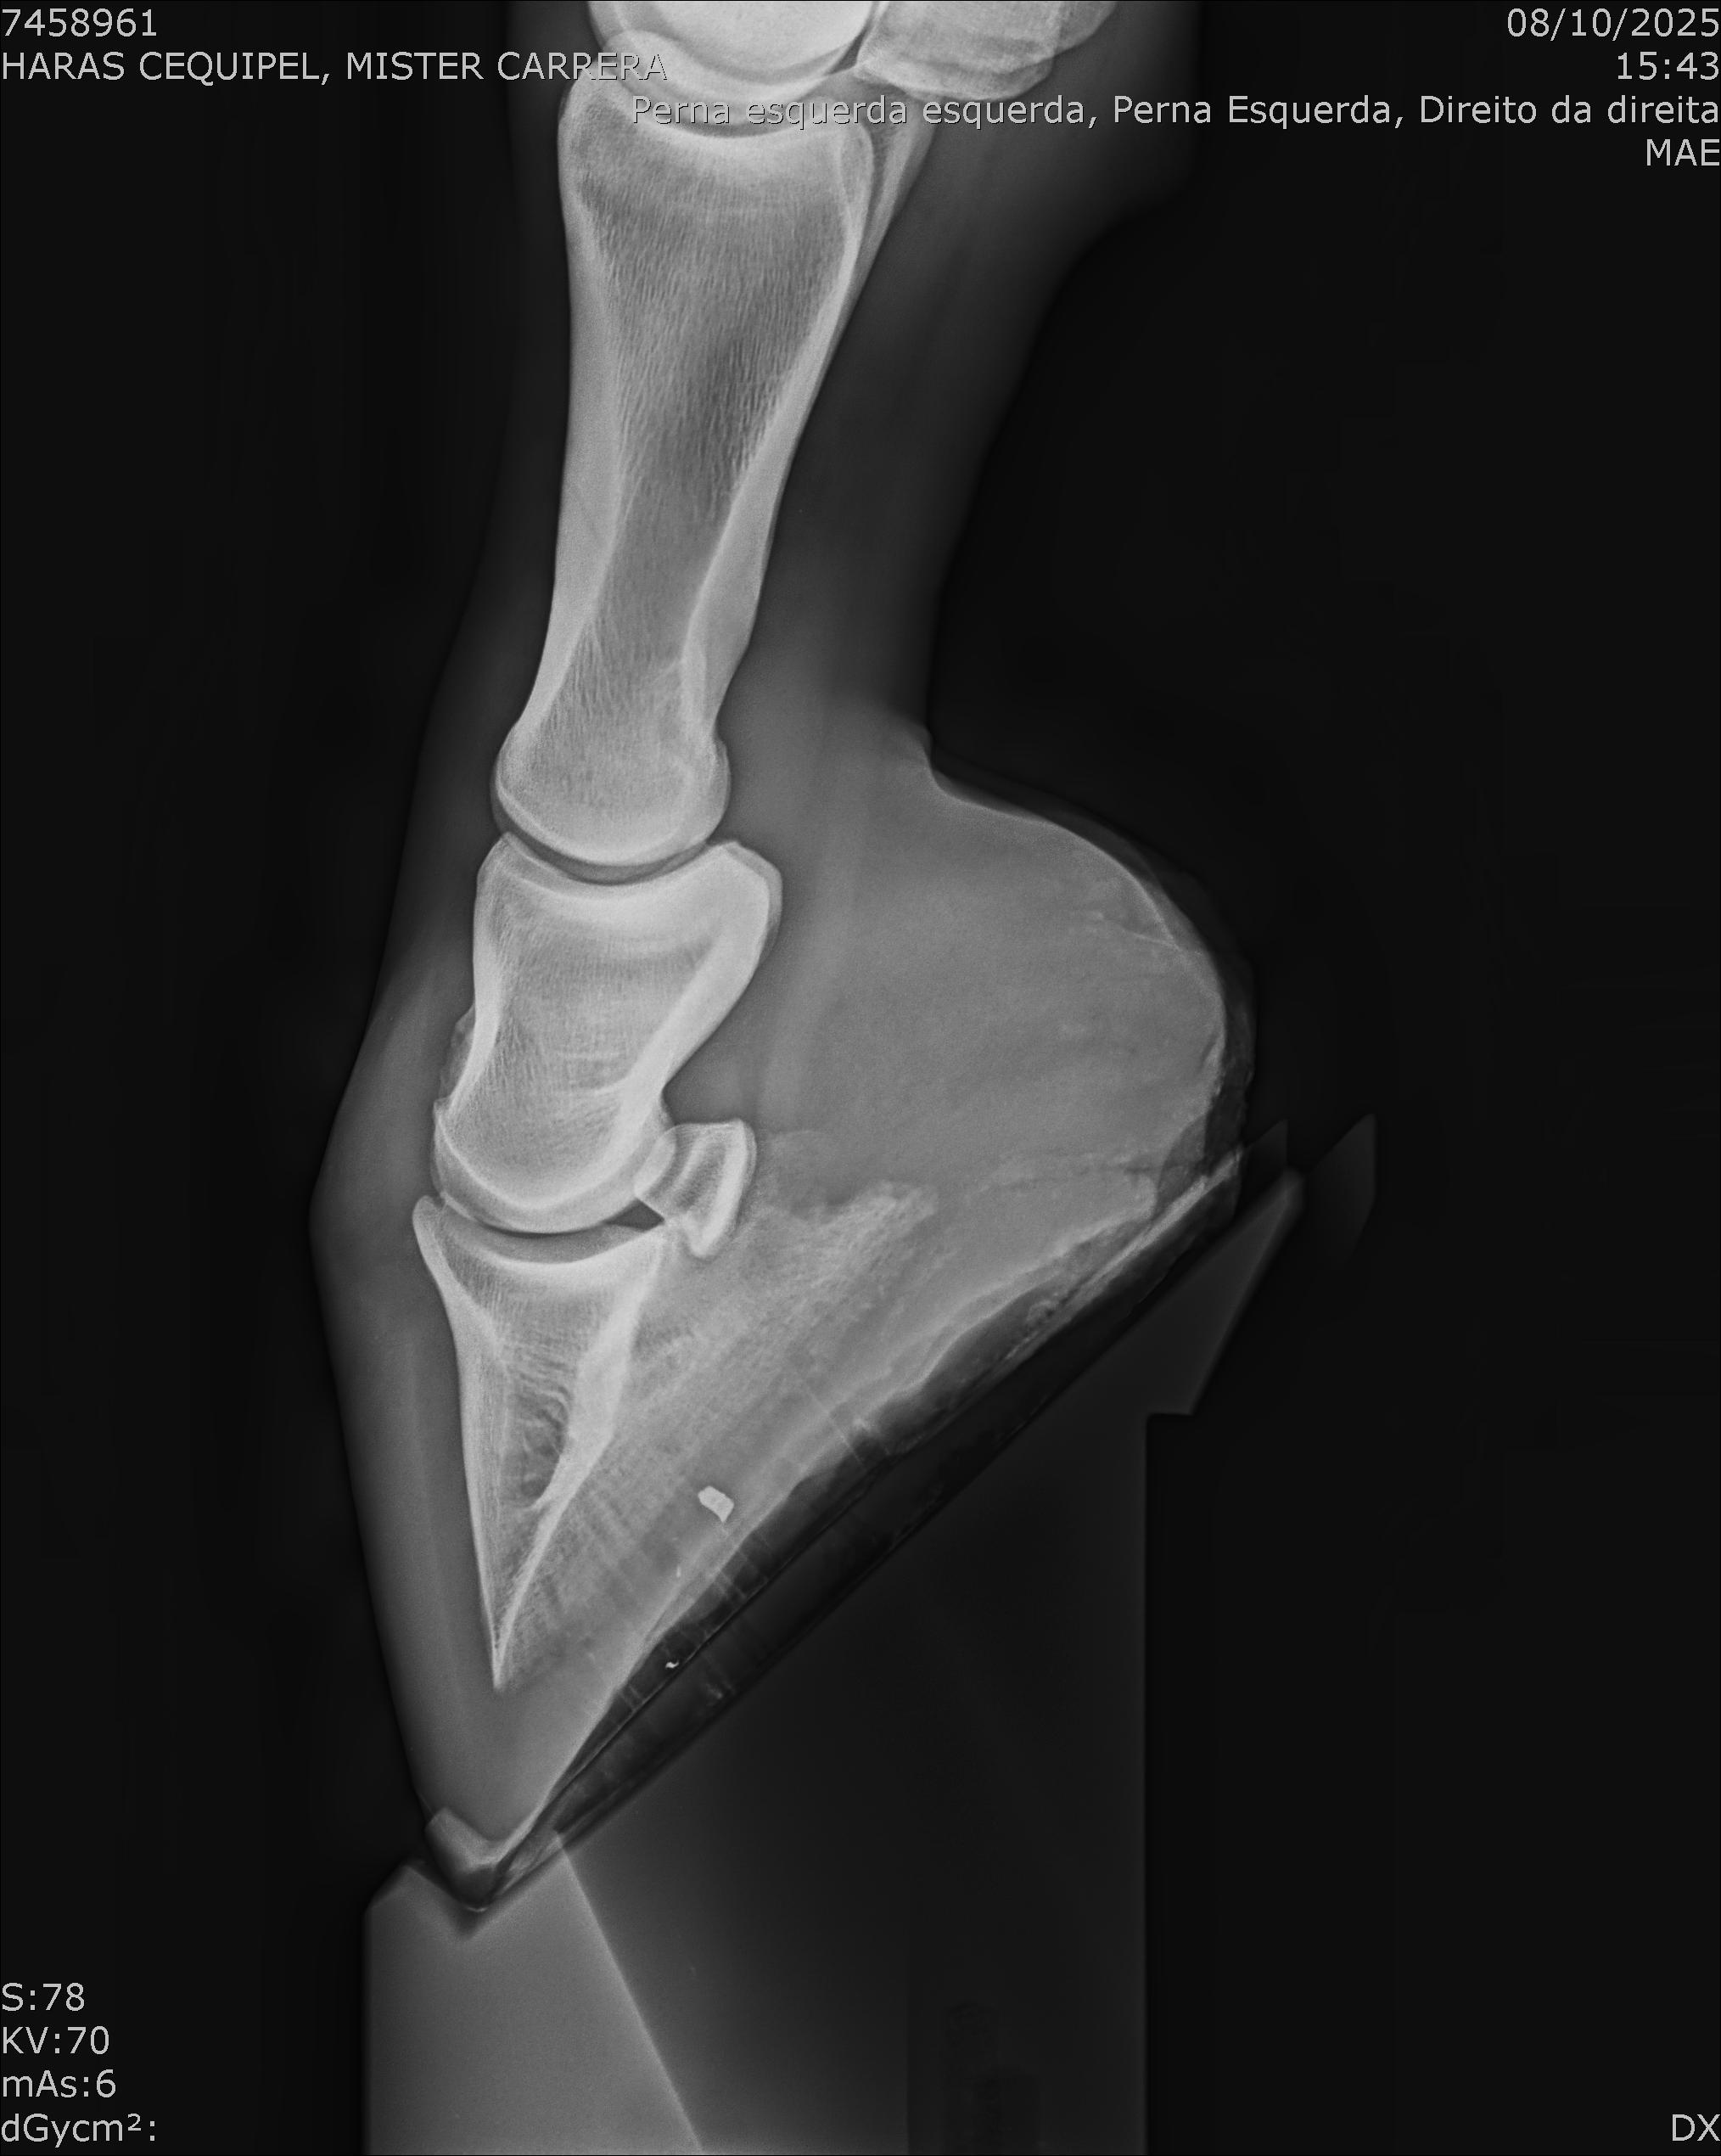

:: RAIOS-X DO LOTE